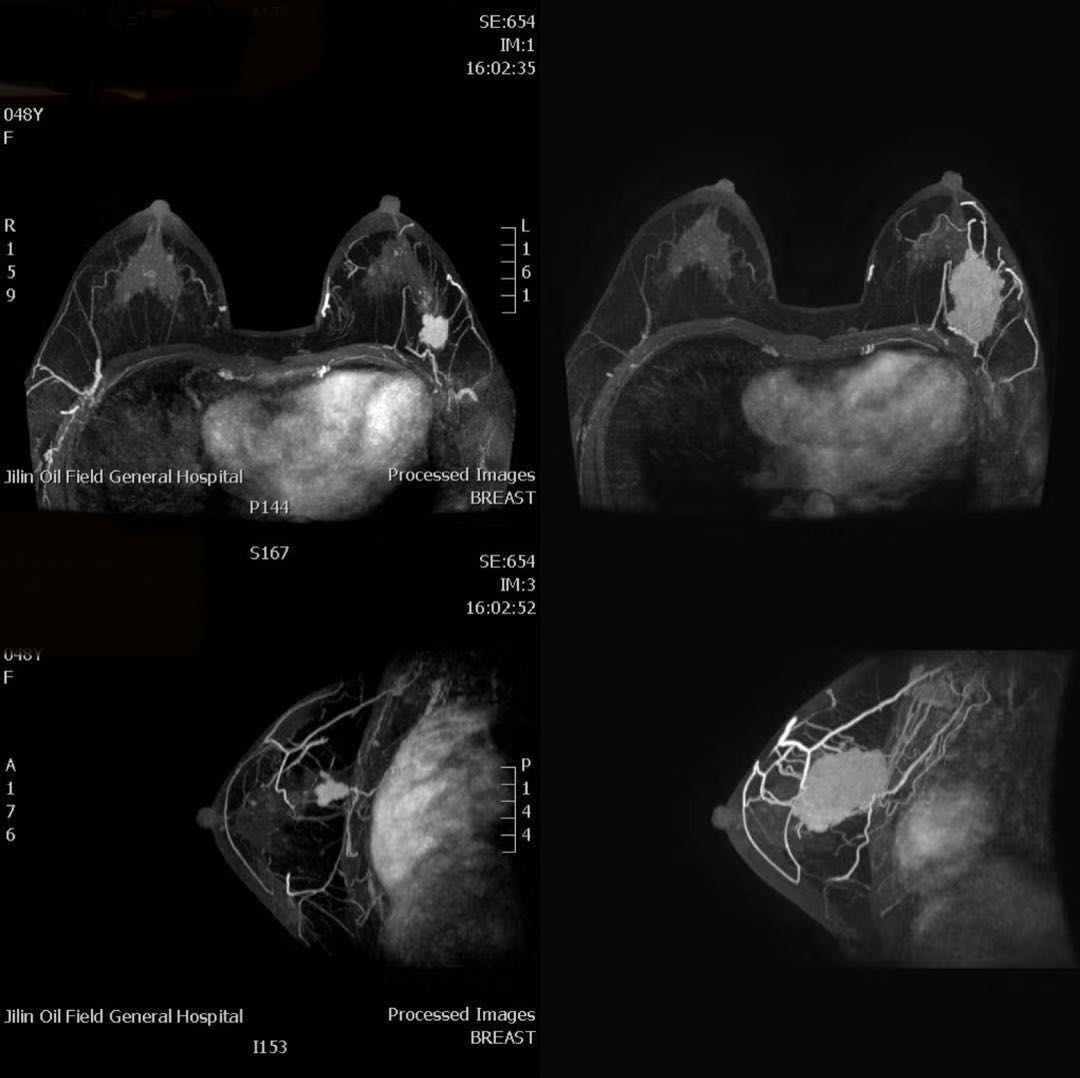

8.新辅助化疗效果评价

在晚期乳腺癌的情况下,许多中心采用在手术前通过新辅助化疗减少肿块的方案。在这种情况下,建议 MRI 用于早期预测化疗期间的反应或用于术前评估 。新辅助化疗前应进行基线 MRI 评估,因为 MRI 图像无法与初始乳房 X 线摄影或超声检查进行比较。然而,女性应该意识到,如果在化疗结束时使用 MRI 来指导手术,一小部分患者 (10-20%) 可能会在临床上低估或高估残留的癌症。